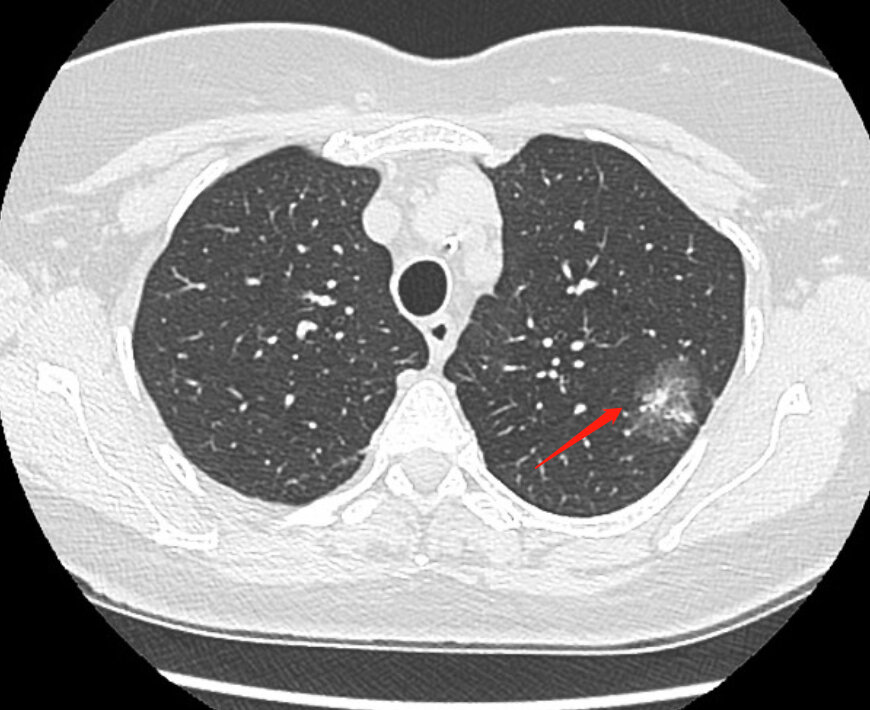

熟记这些ct表现,一眼识破 "转移性肺癌"!